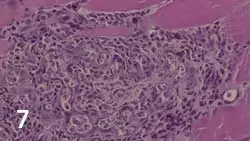

Merogony occurs in tissues of the canine host (Figure 6A, H americanum; Figure 6B, H canis). Released merozoites provoke pyogranulomatous inflammation and vasculitis (Figure 7) that may lead to hypertrophic osteopathy (Figure 8) with ACH. Merozoites enter neutrophils to become gamonts.